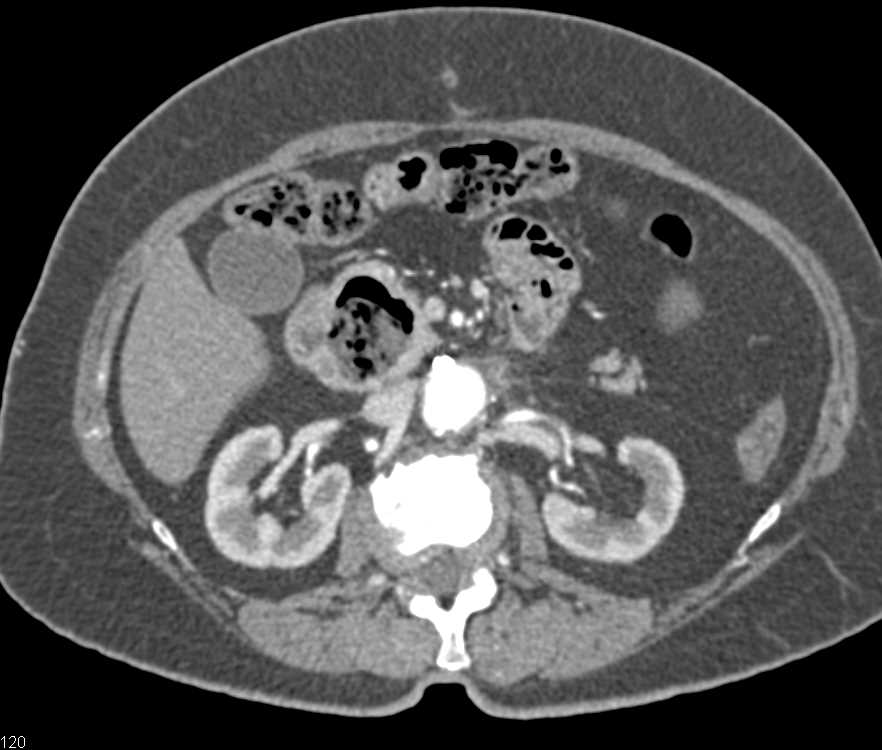

Duodenal Adenocarcinoma in D2